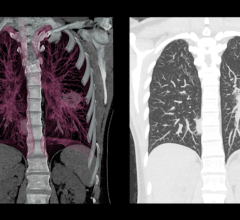

“Lung cancer is the deadliest cancer in men and in women, and it all boils down to how it is detected and when it is ...